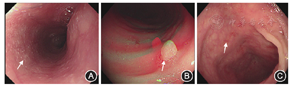

辅助检查(括号内为参考值范围):血常规示白细胞计数10.1×109/L[(5.0~12.0)×109/L]、嗜酸粒细胞计数0.75×109/L[(0.05~0.50)×109/L]、嗜酸粒细胞百分比0.075(0.005~0.050)、血红蛋白59 g/L(120~140 g/L)、血小板计数640×109/L[(125~350)×109/L]。粪常规示褐色稀糊便,白细胞1~2个/高倍镜视野,红细胞2~3个/高倍镜视野,粪隐血阳性,虫卵未检出,见大量真菌,粪便艰难梭菌毒素阴性。3次粪培养均阴性。红细胞沉降率52 mm/1 h(0~15 mm/1 h)。(1,3)-β-D葡聚糖838 ng/L(0~60 ng/L)。血总IgE 4560×103 U/L[(0~199)×103 U/L]。尿常规、肝肾功能、电解质、心肌酶、C反应蛋白、降钙素原均正常。抗链球菌溶血素O、类风湿因子、抗核抗体、抗中性粒细胞胞质抗体、血巨细胞病毒DNA定量、EB病毒DNA定量、体液免疫、细胞免疫、结核分枝杆菌DNA、结核分枝杆菌抗体、肝炎病毒系列、梅毒抗体、人免疫缺陷病毒抗体均阴性。结核斑点试验、结核菌素试验、曲霉菌半乳甘露聚糖检测阴性。腹部B超示右侧结肠区肠壁黏膜层增厚,回声增强,考虑出血性炎症改变;腹腔积液,下消化道积粪,未见肠套叠及梗阻征象;肝胆胰脾未见异常,可见数枚系膜淋巴结。腹部CT示升结肠肠壁水肿增厚。胸部CT平扫未见明显异常。胃十二指肠镜下食管可见白色斑点状物附着(图1A),盐水冲洗不易脱落,慢性浅表性胃炎。结肠镜提示结肠息肉(图1B),结肠炎(图1C)。肠道病理活检示可见黏膜内浆细胞、淋巴细胞、嗜酸粒细胞及中性粒细胞浸润,形态提示组织包浆菌感染(图2A),碘酸雪夫(PAS)染色阳性(图2B)。消化系统疾病易感基因检测示胱天蛋白酶募集域蛋白9(caspase recruitment domain-containing protein 9,CARD9)基因c.1204_1205insC(p.C402Sfs*2)和c.1118G>C(p.R373P)复合杂合突变(图3)。